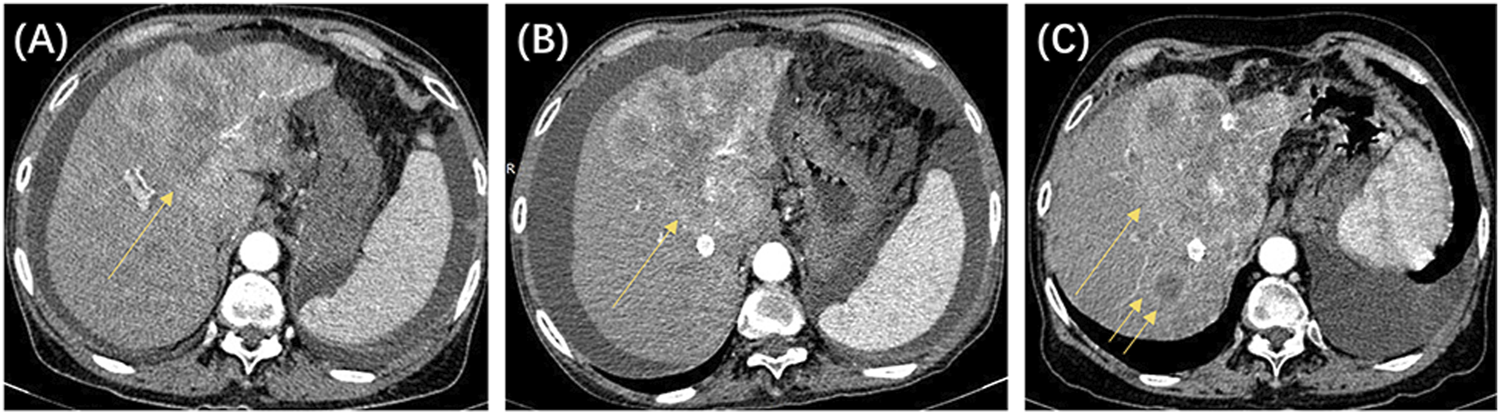

In this study, we identified 109 patients with HCC with BCLC stage A or B who initially underwent the DEB-TACE procedure at our hospital. After excluding 16 patients who did not meet the inclusion criteria, 93 patients were finally included in the study (Figure 1). Table 2 shows the baseline clinical and radiologic information of patients. The median follow-up period was 958 days (95% CI: 757–1,159). Based on the definition of UP, 77 (82.8%) patients developed UP; among them, 42 (54.5%) developed multiple intrahepatic nodules following treatment, and subsequent locoregional interventional therapy failed to induce tumor remission; 11 (14.3%) developed extrahepatic metastasis; 3 (3.9%) maintained SD after two continuous interventions (Figure 2); 13 (16.9%) developed vascular invasion (Figure 3); 2 (2.6%) had hepatic function progress from grade A or B to grade C; and 6 (7.8%) patients had primary tumor enlargement by >20%, and subsequent locoregional interventional therapy did not induce tumor remission.

FIGURE 2

The patient was a 64-year-old woman, with a clinical diagnosis of hepatocellular carcinoma, Barcelona Clinic Liver Cancer stage B, and pre-treatment hepatic function of the Child–Pugh grade (B). The above shows the contrast-enhanced CT images before and after locoregional interventional therapy. (A) Image taken before the initial drug-eluting beads transcatheter arterial chemoembolization (DEB-TACE) procedure, showing that the left liver lobe is full of blood-supplying, space-occupying lesions (single arrow). (B) CT image 8 weeks after the initial TACE procedure. Significant enhancement was still seen for the target tumor (single arrow). The target tumor was assessed to be stable disease based on modified response evaluation criteria in solid tumors (m-RECIST) criteria. (C) CT image 8 weeks after the second TACE procedure. Significant enhancement was still seen for the target tumor (single arrow), and new intrahepatic nodules were seen (double arrows). The target tumor was assessed to be progressive disease based on m-RECIST criteria. According to the untreatable progression (UP) criteria, the patient did not achieve an objective response after two DEB-TACE treatments and was determined to have UP.